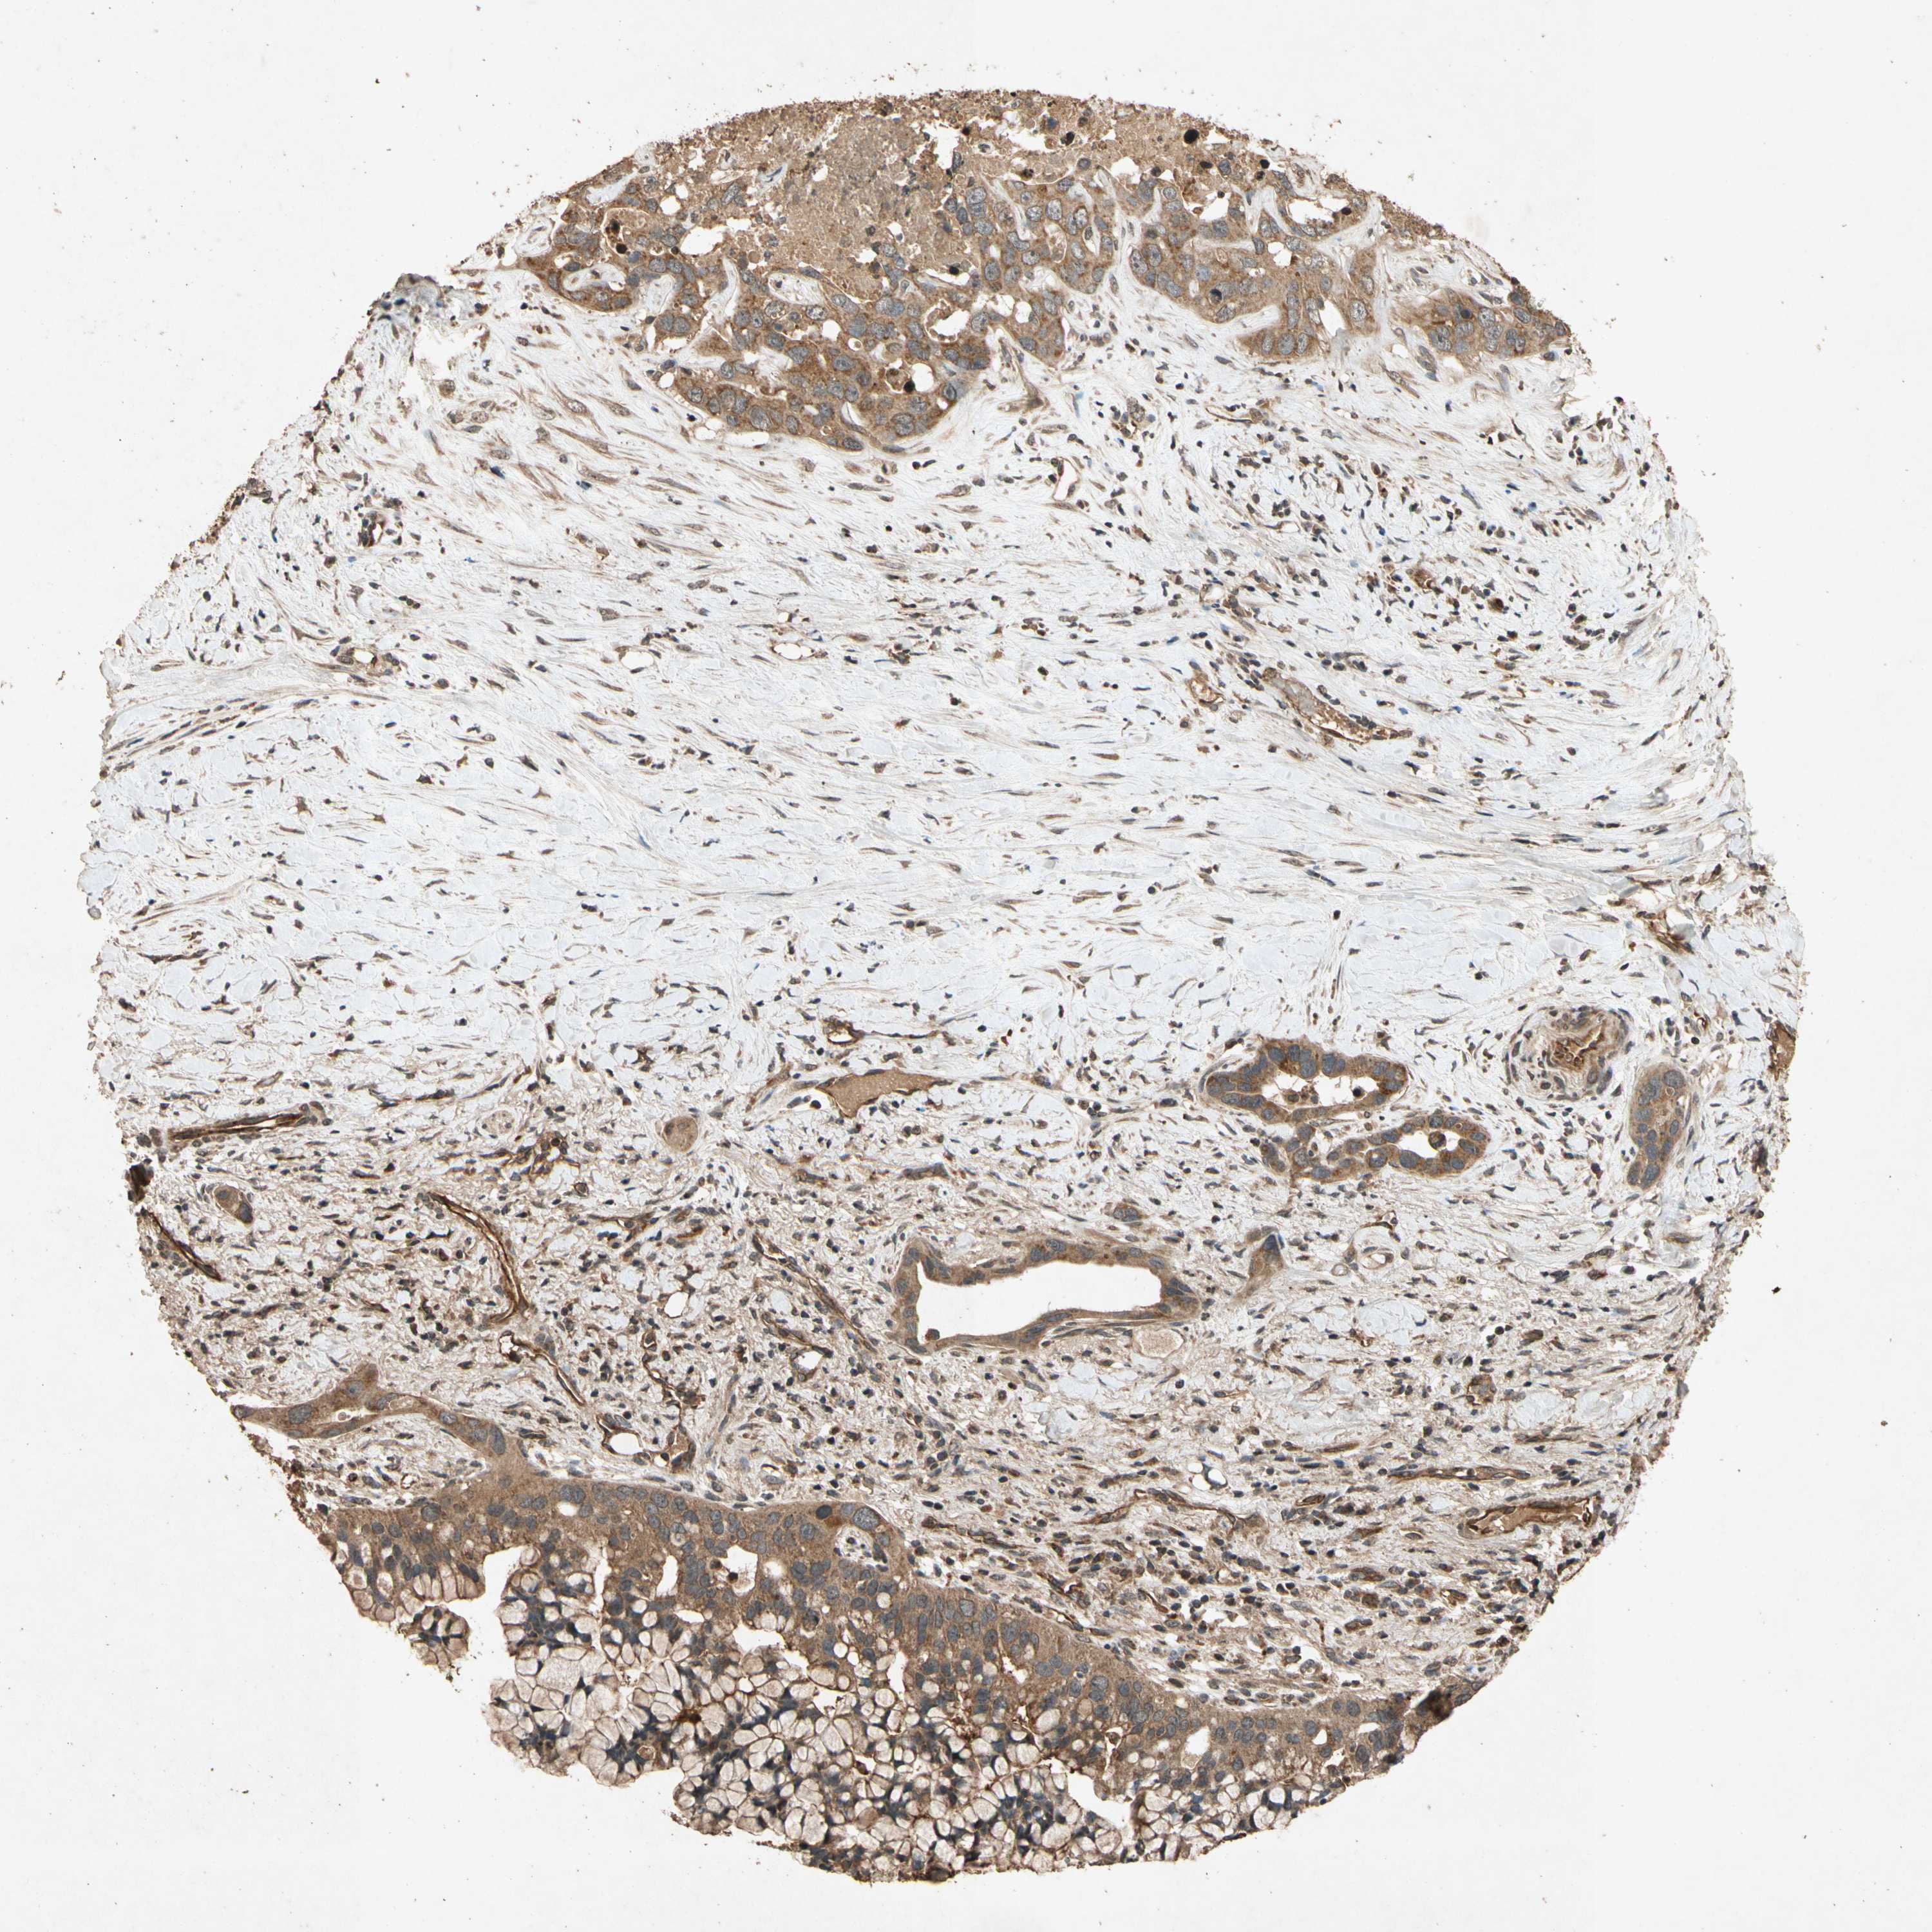

LIVER CANCER - Protein expressioni

A mouse-over function shows sample information and annotation data. Click on an image to view it in a full screen mode. Samples can be filtered based on level of antibody staining by selecting one or several of the following categories: high, medium, low and not detected. The assay and annotation is described here.

Note that samples used for immunohistochemistry by the Human Protein Atlas do not correspond to samples in the TCGA dataset.

Antibody stainingi

Antibody staining in the annotated cell types in the current human tissue is reported as not detected, low, medium, or high, based on conventional immunohistochemistry profiling in selected tissues. This score is based on the combination of the staining intensity and fraction of stained cells.

Each image is clickable and will lead to virtual microscopy that enables deeper exploration of all samples and also displays staining intensity scores, fraction scores and subcellular localization as well as patient and tissue information for each sample.

Antibody HPA000994

Antibody CAB008681

Staining

High

Medium

Low

Not detected

Intensity

Strong

Moderate

Weak

Negative

Quantity

>75%

75%-25%

<25%

None

Location

Nuclear

Cytoplasmic/membranous

Cytoplasmic/membranous,nuclear

Carcinoma, Hepatocellular, NOS

Cholangiocarcinoma